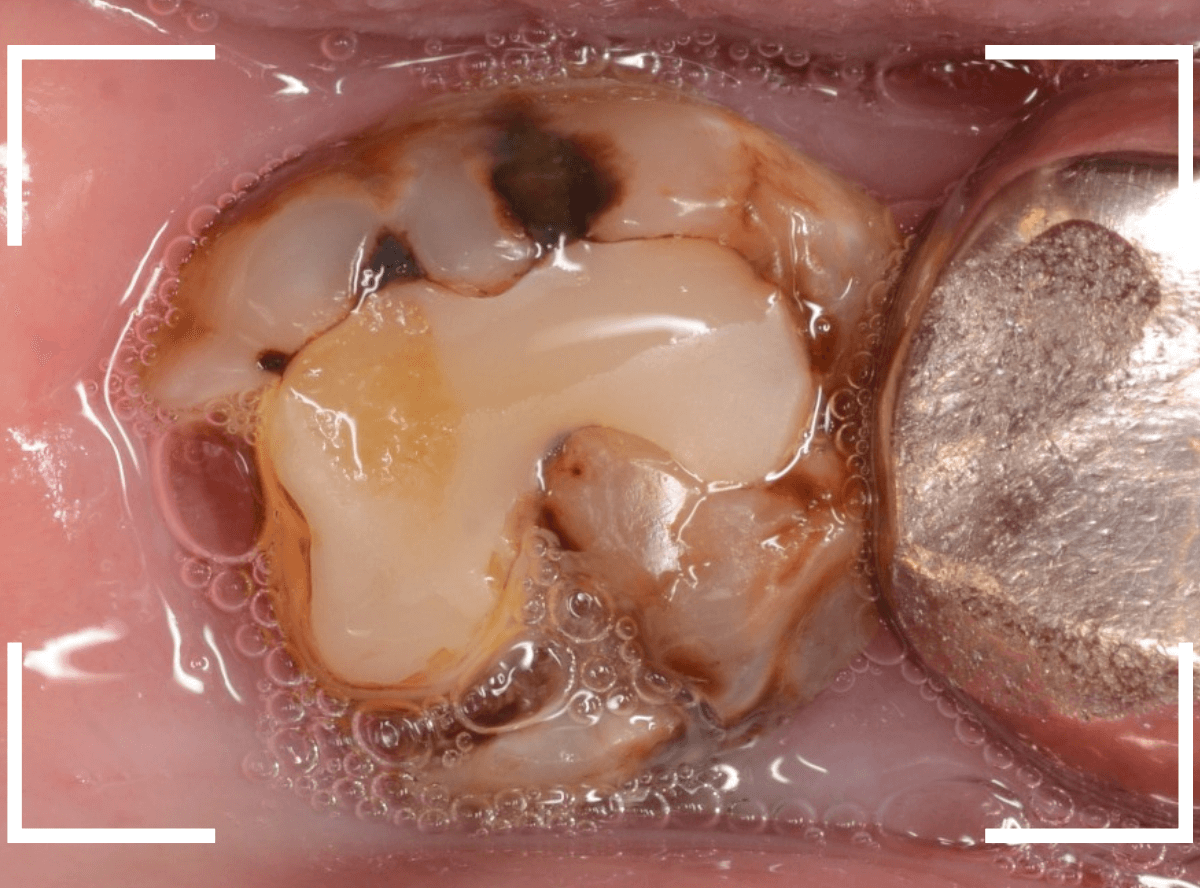

抜歯後に長期間お痛みが出たり、経過観察が必要な難しいおやしらずの抜歯ならまだしも、簡単なおやしらずの抜歯を避けてしまったがために、他の歯に悪影響を与えてしまったもったいない例も多々見てきました。

ここでは、比較的簡単なおやしらずの抜歯の例を中心にご紹介します。

このようなおやしらず、あなたはありませんか?